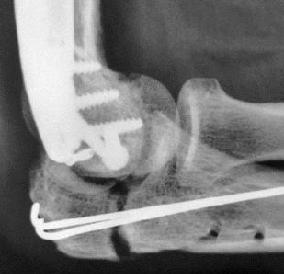

Tratamentul chirurgical și local

Tratamentul chirurgical rămâne esențial pentru îmbunătățirea calității vieții pacienților cu metastaze osoase RCC (47) Procedurile sunt în primul rând paliative, concentrându-se pe stabilizare, controlul durerii și restabilirea mobilității. Chirurgia este indicată în mod obișnuit pentru fracturi patologice sau iminente (fig 1), compresia măduvei spinării sau leziuni solitare adecvate pentru metastasectomie (48,49) .

Deoarece metastazele RCC sunt hipervasculare, embolizarea arterială preoperatorie (fig.2) a devenit standard pentru a minimiza sângerarea intraoperatorie. Embolizarea completă poate reduce pierderea de sânge cu până la 50% și poate simplifica rezecția chirurgicală (50)

Când distrugerea osoasă duce la compromiterea structurală majoră, înlocuirea endoprotezică folosind proteze modulare sau personalizate oferă stabilitate durabilă (51). Augmentarea cu polimetil metacrilat (PMMA) asigură fixarea imediată și ameliorarea durerii prin exercitarea unei necroze termice locale asupra celulelor tumorale (52) . În cazurile cu încărcătură limitată a bolii, metastasectomia a fost asociată cu o supraviețuire prelungită, în special atunci când se realizează rezecția completă și nu există răspândire viscerală (fig.3) (53)